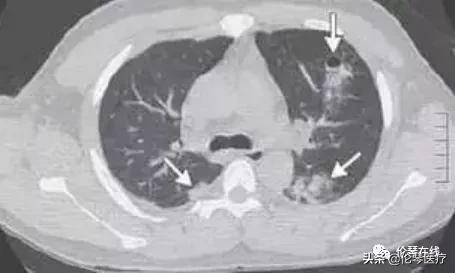

右肺多發囊狀、穴窟樣低密度影和小片狀滲出

多發空洞,呈“隧道徵”

雙肺斑片狀滲出,並可見小囊狀影